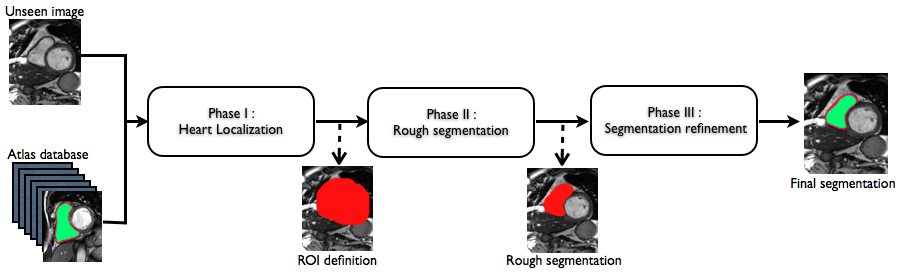

Instead of applying only once the multi-atlas propagation framework to an unseen image, we use a coarse-to-fine strategy that incrementally refines the segmentation by means of the multi-atlas propagation. The coarser segmentation obtained at each propagation level is used as a mask to start the registration gradually up to the finest level. The different steps of our coarse-to-fine strategy, illustrated in Fig. 2, are described in the following.

Phase I. Heart localization.

At a first stage, we seek to define a region of interest (ROI) that encloses the heart in the unseen image. At this phase, the unseen image is globally registered to the atlases using a block matching approach [8]. The obtained transformations are applied to the atlas’ label images, which are all fused using majority voting. Figure 2 shows the typical output ROI for the whole heart.

Phase II. Rough segmentation.

The unseen image ROI obtained from phase I is used as a mask in the registration step of phase II. The use of a mask allows the removal of structures surrounding the heart, e.g. the liver and the ribs, that can affect the registration procedure.

At this phase, two different registration steps are perfomed. The atlas are rigidly registered [8] to the masked unseen image, followed by a non-rigid alignment using a fast free form deformation algorithm [9]. After non-rigidly transforming the atlases, i.e. both intensity and label images, to the unseen image space, we apply an NCC-based ranking strategy [7] in order to determine for each unseen slice which are the most suitable registered atlases slices to use. We selected only the 10% best ranked atlases as several of the registrations fail to provide a good alignement of the unseen image and the atlases. The selected atlases slices were then fused using the STEPS algorithm [7] in order to obtain an initial RV rough segmentation (Fig. 2). As at this stage only the top 10% atlases are used, the results from thie fusion step still don’t have a high quality.

Phase III. Segmentation refinement.

In order to accurately initialize an affine registration for all the atlases, all the label images are affinely aligned [8] to the estimated rough segmentation. The transformed label images are fused through majority voting. As in phase II, this mask is used to remove surrounding structures in the final image-to-image non-rigid registration. With the non-rigid transformations, the label images are propagated and resampled using a nearest neighbor interpolation to preserve the binary nature of the segmentations. Finally, we make use of the multi-label fusion algorithm [7] that first ranks every atlas slice based on the NCC and then fuses locally the labels of the N best ranked atlases .

Table 1 summarizes the different registration and fusion algorithms involved at each phase of the coarse-to-fine strategy.